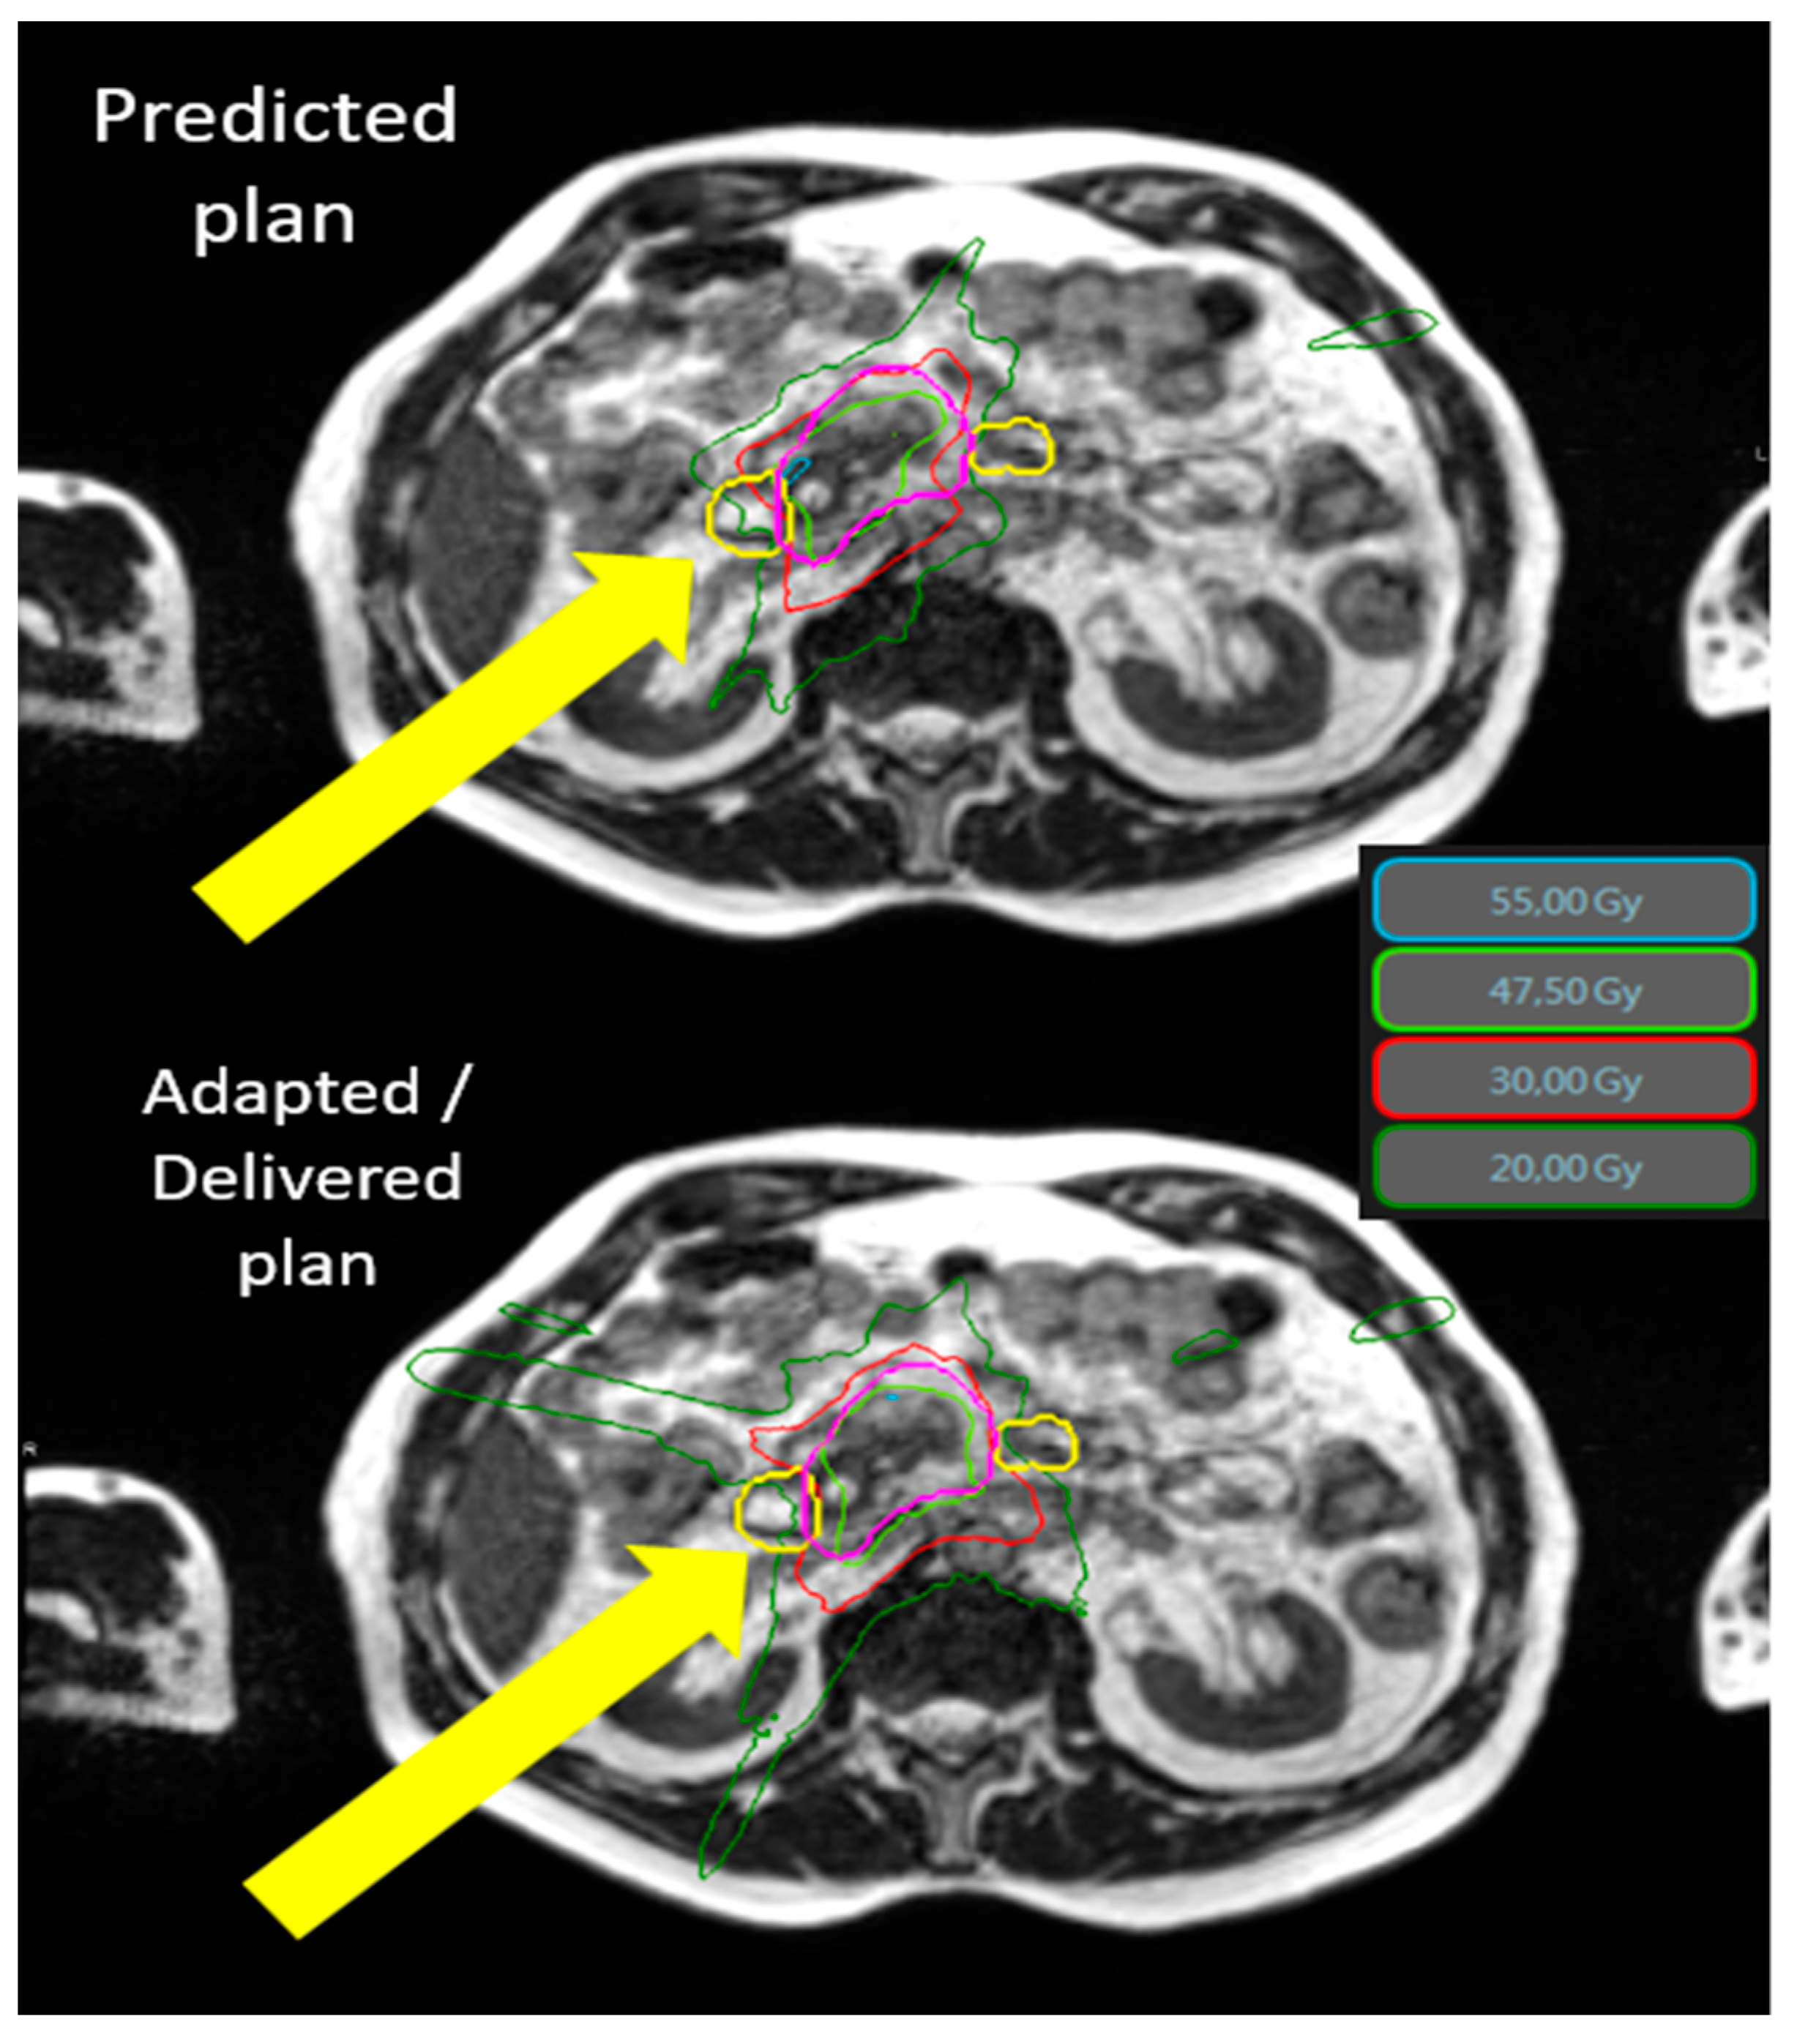

2.2. Radiotherapy Planning and Delivery

3.3. Dosimetric Benefits of Adaptive Treatments